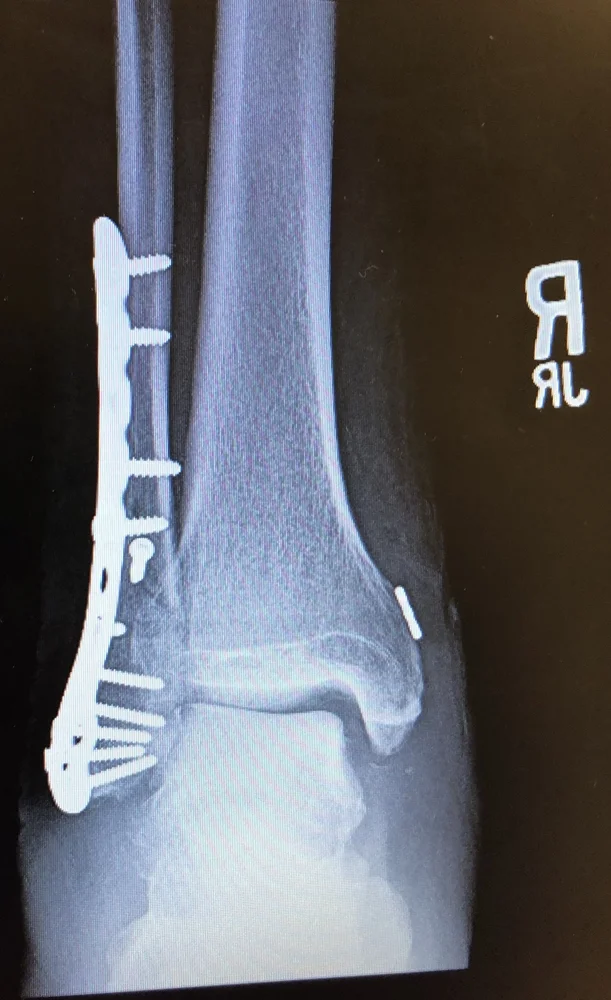

Worst one was my left fibula just last year (my first at-fault accident in 47 years riding), barely clipped a lady's rear bumper on a big Honda trike. Foot ended up pointing to like 2:00. Still gimpy one year and 10 days later, but more or less normal. A plate and over a dozen screws in there, plus some kinda wire thingy because a tendon pulled loose off the bone. It takes me a while for my ankle to get going, and my leg tires out after 5 or 6 hours; I used to be able to work 10 hours a day every day and just be overall/generally tired. No more. Riding is not an issue, though, the ankle has regained full riding range.